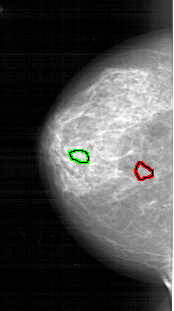

FILE: A_1744_1.LEFT_CC.OVERLAY

TOTAL_ABNORMALITIES 1

ABNORMALITY 1

LESION_TYPE CALCIFICATION TYPE PLEOMORPHIC DISTRIBUTION CLUSTERED

ASSESSMENT 4

SUBTLETY 2

PATHOLOGY BENIGN

TOTAL_OUTLINES 1

BOUNDARY

ABNORMALITY 2